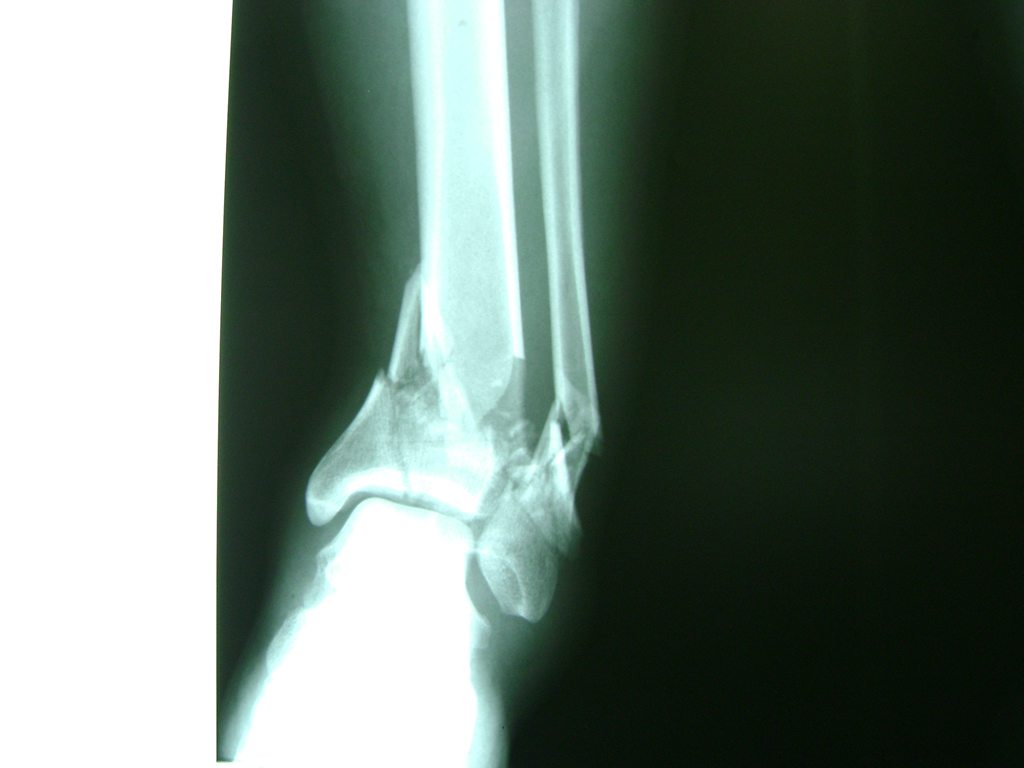

Una fractura de tobillo es la rotura de uno o más de los huesos del tobillo. Estas fracturas pueden ser:

- Parciales (el hueso está sólo parcialmente fisurado, no del todo).

- Completas (el hueso está perforado y está en 2 partes).

- Producirse en uno o ambos lados del tobillo.

Algunas fracturas de tobillo pueden requerir cirugía si:

- Los extremos de los huesos están desalineados entre sí (desplazados).

- La fractura se extiende hasta la articulación del tobillo (fractura intra-articular).

- Los tendones o ligamentos (tejidos que sujetan los músculos y los huesos entre sí) están rotos.